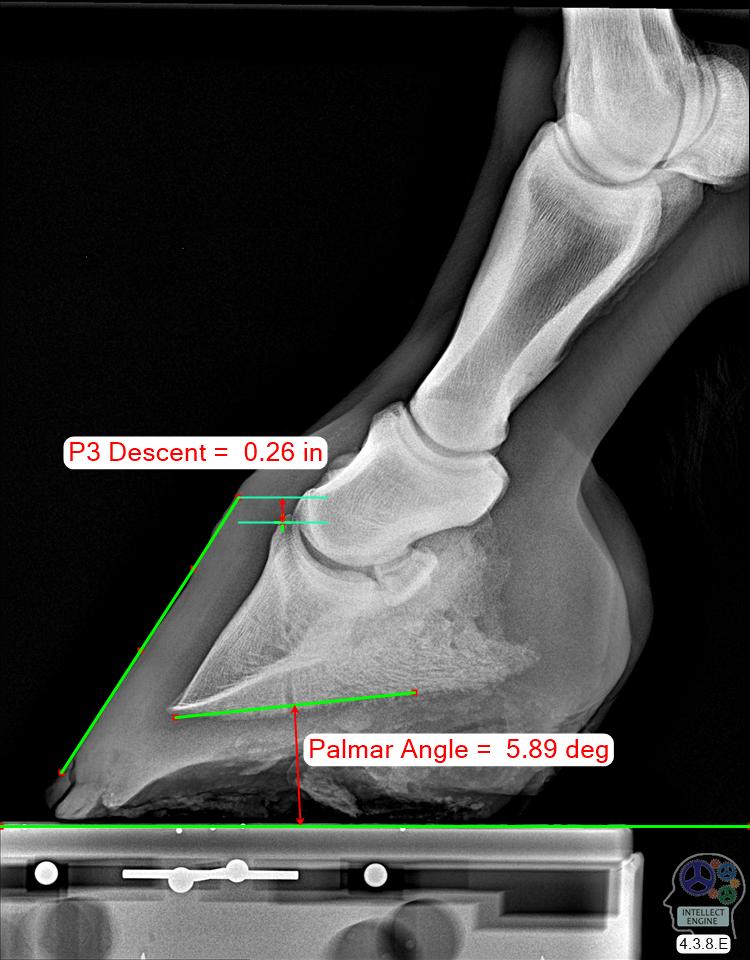

Epona Podiatry Center, LLC Name: Onesy Owner: Ashton Smith Owner ID: Species: Equine Breed: --Unknown--

Sex: --Unknown-Age: 12 Patient ID: Date: 14-Feb-2022

This report is a computer-generated analysis of one or more images and does not constitute a diagnosis. The diagnosis is made only by your veterinarian.